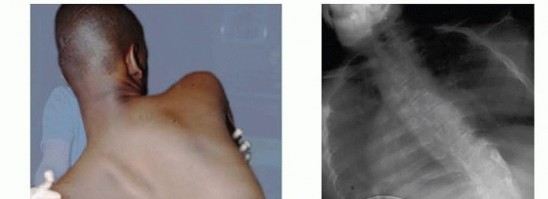

Anterior Interbody Arthrodesis with Instrumentation for Scoliosis DEFINITION Thoracic scoliosis and thoracolu…

Spinal Fusion for Neuromuscular Scoliosis DEFINITION Neuromuscular diseases are heterogeneous between and wit…

Pelvic Fixation for Neuromuscular Scoliosis DEFINITION Neuromuscular scoliosis (NMS) is a spinal deformity in…